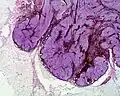

Imagen histológica de un nevo azul celular (2x) -

Forma maligna de un nevo azul. Todos los cortes histológicos están en la tinción hematoxilina-eosina.